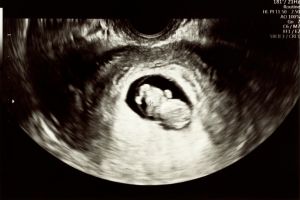

سونوگرافی NT یا سونوگرافی اندازهگیری ضخامت نیمه شفاف پشت گردن جنین (Nuchal Translucency) یکی از آزمایشهای کلیدی غربالگری سه ماهه اول بارداری محسوب میشود که معمولاً بین هفتههای ۱۱ تا ۱۳ انجام میگیرد. در این روش با تصویربرداری دقیق ضخامت فضای شفاف پشت گردن جنین سنجش میشود که افزایش این ضخامت میتواند نشانهای از برخی اختلالات کروموزومی مانند سندرم داون، تریزومی ۱۳ و ۱۸ باشد. سونوگرافی NT کاملاً غیرتهاجمی و بدون درد بوده و نقش مهمی در ارزیابی سلامت جنین ایفا میکند. این آزمایش در کنار آزمایش خون مادر و سایر معیارهای غربالگری به متخصصین کمک میکند تا ریسک ابتلا به ناهنجاریهای ژنتیکی را به طور دقیقتر تخمین زده و در خصوص مراحل بعدی مراقبت تصمیمگیری نمایند.